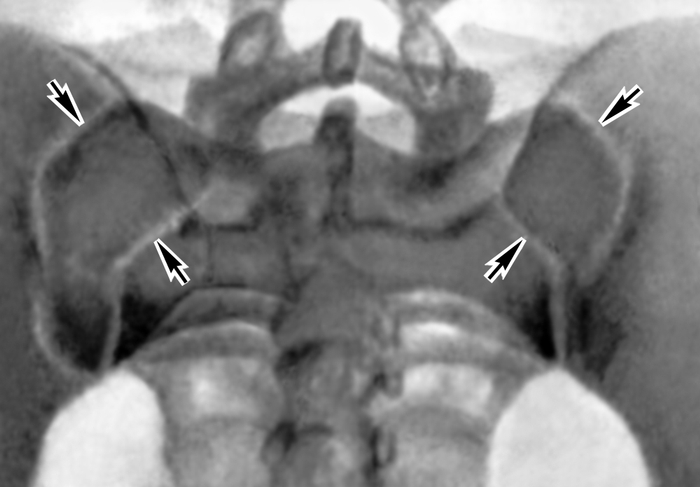

Рентгенограмма крестцово-подвздошных суставов в норме (прямая задняя проекция)